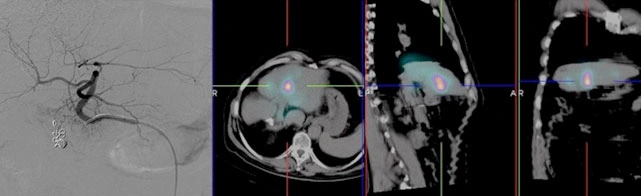

Un altro tipo di tumore del fegato, più raro, è il carcinoma fibrolamellare. Questa forma di cancro è generalmente diagnosticata in pazienti giovani e, rispetto al carcinoma epatocellulare, tende ad essere meno invasiva e a crescere in modo più ben delimitato. Una caratteristica distintiva del carcinoma fibrolamellare è la presenza di una lesione fibrotica centrale, visibile attraverso tecniche di diagnostica per immagini come la risonanza magnetica o la tomografia computerizzata (TC).

Sebbene si tratti di una forma rara, il carcinoma fibrolamellare viene trattato nella maggior parte dei casi come il carcinoma epatocellulare, con approcci terapeutici che possono includere chirurgia, trapianto di fegato, chemioembolizzazione o terapia sistemica.